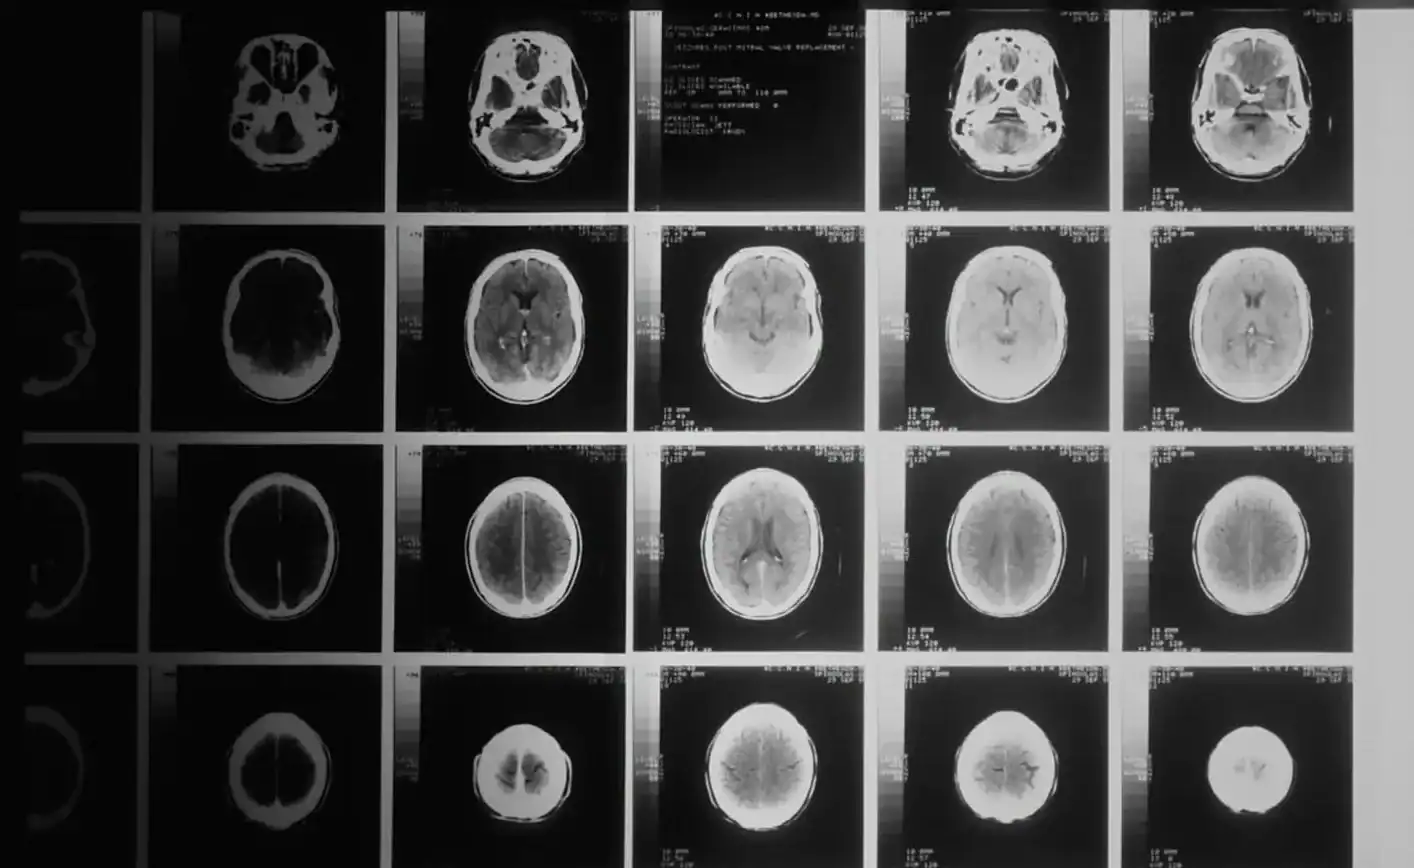

Lucas Jemeljanova , de 13 anos, entrou para a história da medicina ao se tornar o primeiro paciente no mundo a ser curado de um tipo altamente agressivo de câncer cerebral. Natural da Bélgica, ele foi diagnosticado aos seis anos com glioma difuso intrínseco da ponte (DIPG), um tumor raro que afeta o tronco cerebral e é responsável por 98% das mortes de pacientes em até cinco anos após o diagnóstico.

“Lucas desafiou todas as probabilidades”, afirmou Jacques Grill, médico responsável pelo programa de tumores gerais do Instituto Gustave Roussy, em entrevista à AFP. Segundo o especialista, nunca houve registro de caso semelhante na literatura médica. “Em sucessivas ressonâncias, vi o tumor desaparecer completamente” , contornou.

Os pesquisadores descobriram que o tumor de Lucas apresentou uma mutação rara que pode tornar a doença mais sensível ao medicamento. Outros sete pacientes que participaram do mesmo estudo apresentaram melhora clínica, mas apenas tiveram regressão total da doença.

Localizado na base do cérebro, o DIPG afeta funções como respiração, deglutição e equilíbrio. Em geral, o prognóstico é de apenas nove meses de vida. Por isso, o caso de Lucas é visto como um marco científico e uma esperança para famílias que enfrentam o diagnóstico.